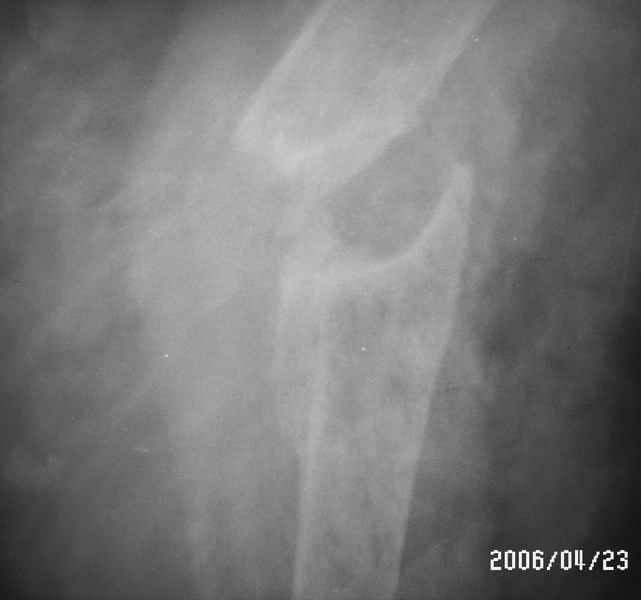

Уважаемые коллеги! Помогите в выборе тактики лечения больной Р.,56 лет, с болтающимся ложным суставом с/3 правой плечевой кости 2-х летней давности. В анамнезе - бронхиальная астма, гормонозависимая форма, ожирение III cт. Травма - автодорожная, получила закрытый многооскольчатый перелом диафиза плечевой кости со смещением (от метафиза до метафиза), в экстренном порядке нами произведен закрытый остеосинтез стержневым аппаратом, отломки удалось сопоставить анатомически. В дальнейшем больная выпала из поля зрения. Как потом выяснилось, после снятия стержневого аппарата, больная долечивалась по Илизарову специалистом из г. Кургана. Аппарат Илизарова удален из-за нагноения мягких тканей. Последние два года работая бухгалтером, фиксирует плечо ортезом. Теперь вновь обратилась к нам для ликвидации ложного сустава.

Есть вариант открытого вмешательства с резекцией зоны ложного сустава, костной пластикой и накостным остеосинтезом хорошей пластиной, в смысле мощной и длинной.